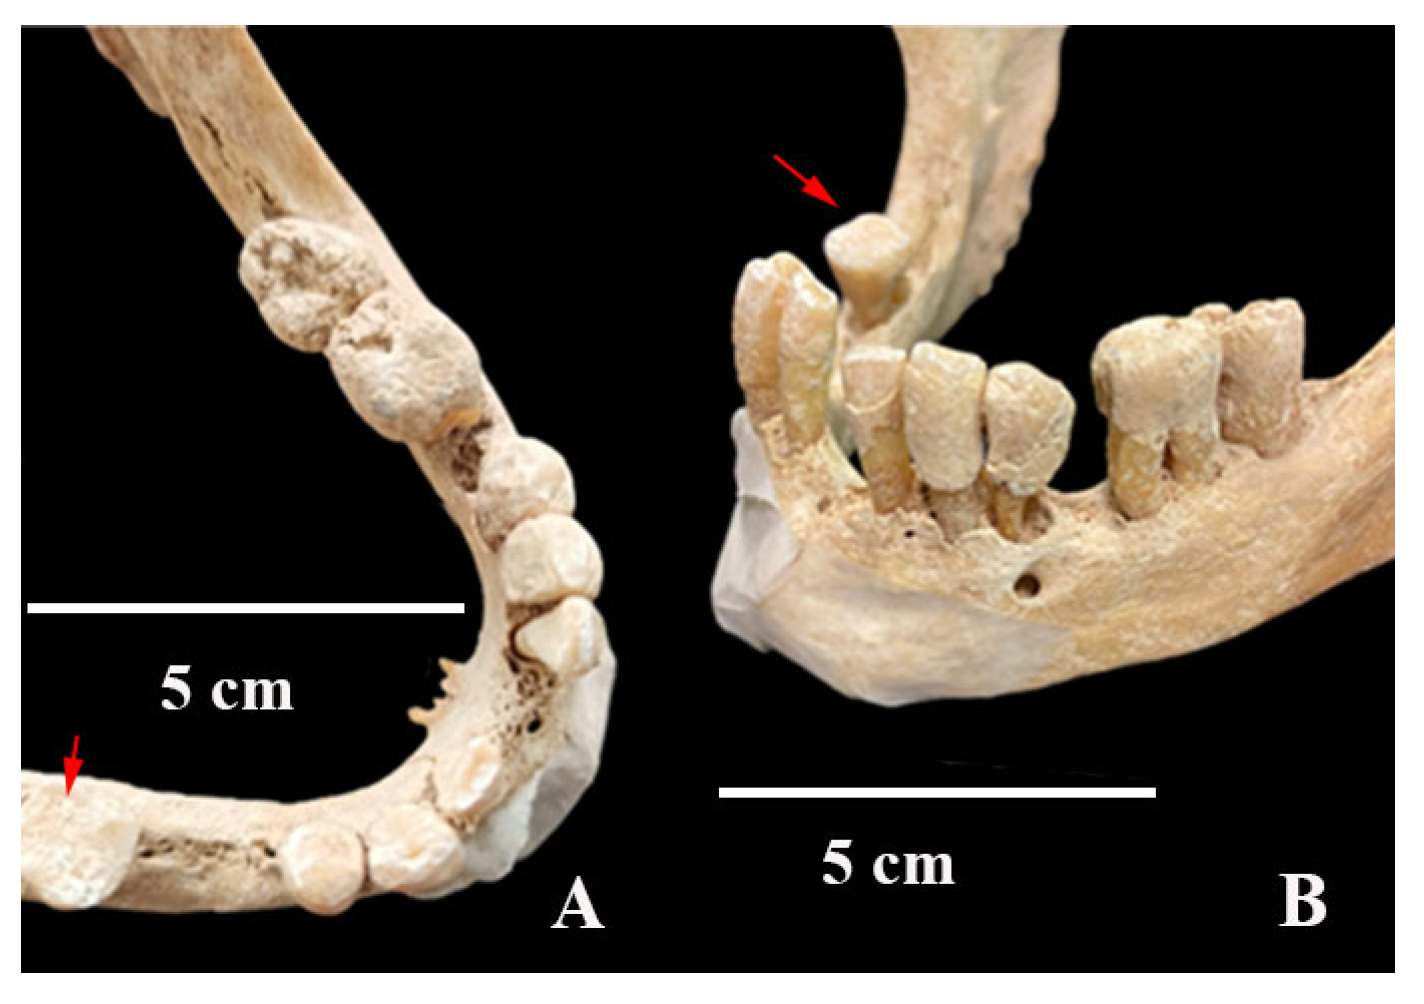

Figure 8.

Superior (A) and antero-lateral (B) views of the T4.2 mandible, highlighting the presence of tartar on the occlusal, labial, and lingual surfaces of the teeth. The lower right second molar shows wear (red arrow).

Examination of the splanchnocranium (Table A2), along with the skull, revealed an outward inclination of the incisors (Figure 7) and normal orbital dimensions, with a height of 31 mm and a breadth of 32 mm (Figure 7). According to Testut and Latarjet [26], the normal orbital range is 26–48 mm in height and 32–48 mm in breadth, with the lower end of this range being more typical among Spaniards. The mandible was very narrow (dolichognathous), with a mandibular index of 98.3 (Table A2). Absolute values indicate a morphological alteration with an increase in its anteroposterior measurement and a decrease in the laterolateral diameter, as is the case with the cranial measurements. These measurements suggest the presence of type III prognathism. The left hemimaxilla contained the second incisor, canine, and first premolar (the remaining dental elements were lost postmortem). The left hemimandible consisted of the second incisor, canine, first premolar, and first and second molars. The first incisor and second premolar had been lost during life (Figure 8). Examination of the dental elements on the left side highlights the large amount of tartar, which completely covers the lingual, labial, and occlusal surfaces of the preserved elements (Figure 8) and the presence of very little wear. On the right side, the hemimaxilla had retained the two incisors, the canine, and the first premolar (Figure 8). The right hemimandible had preserved the first and second incisors, the canine, and the second molar. The remaining elements of the right hemimandible were lost during life (Figure 8). In contrast to the left side, the right side showed tooth wear and very little tartar (Figure 8 and Figure 9). Significant resorption of the mandibular body was observed (Figure 9). Radiographic images confirm alveolar bone resorption in the mandible, with no evidence of periapical changes (Figure 10). In general, on the left side, the presence of minimal tooth wear and an extreme amount of tartar is notable. This could indicate the left dentition had not been used, probably because of unilateral mastication due to occlusal dysfunction; however, periodontal disease and hygiene differences cannot be excluded.